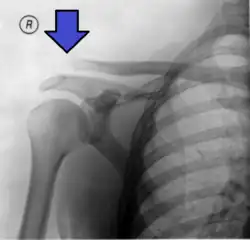

| An Xray showing a separated shoulder. Notice the separation between the end of the collarbone and the scapula. | |

X-ray indicates a separated shoulder when the acromioclavicular joint space is widened (it is normally 5 to 8 mm).[9]